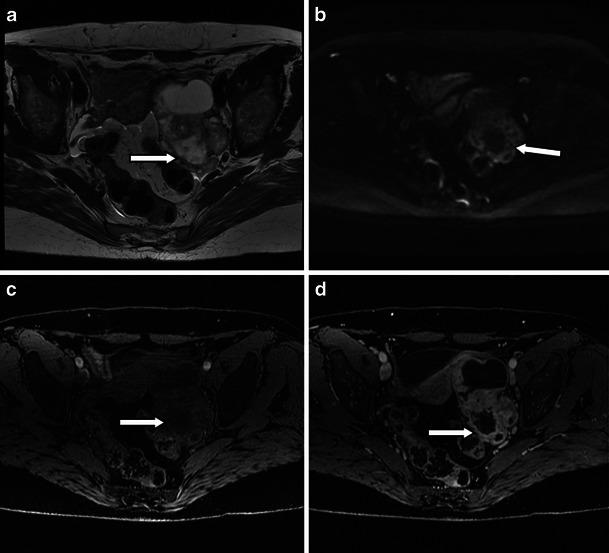

The diagnosis of malignant struma ovarii is usually based on histological features of the resected ovary, as no specific imaging features are available to detect malignant struma. However, as malignant struma ovarii are teratomas, the following criteria apply to detect malignancy: CT and MR imaging findings of malignant transformation of ovarian teratoma include invasive growth of large, irregularly marginated soft-tissue components through the tumour wall or irregular soft-tissue components within the tumour [37] (Figs. 8 and 9). In view of the ascites frequently present in benign struma, distinguishing benign from malignant struma is difficult in the absence of extracapsular extension (Fig. 8). The potential future role of diffusion-weighted imaging to distinguish benign from malignant struma remains to be investigated in a large multicentre trial. In our limited experience ADC values in malignant struma overlapped with those of benign struma. However, in this limited cohort of only two cases, the tumour burden in the struma on histopathology was limited.

Fig. 8.

Three-tesla T2 high-resolution images of a benign and malignant struma ovarii for comparison. a Sagittal image showing the large mixed solid and cystic malignant struma (arrow). b Axial plane image through a benign struma shows an equally complex large lesion (arrow). a, b Ascites is present in both the benign and the malignant case (A)

Fig. 9.

Malignant struma arising from the left ovary in a 40-year-old woman presenting with abdominal distension and lower abdominal pain. CA-125 levels were elevated at 1,075 kU/l (normal value <12 kU/l). a Ultrasound shows a mixed solid cystic mass with predominantly solid features. On the 3-T T2-weighted high-resolution (b), unenhanced (c) and enhanced (d, f) T1 fat-saturated LAVA and diffusion-weighted images b = 1,200 mm/s2 (e), imaging features resemble a mucinous cystadenocarcinoma. d, e The lacy pattern caused by the enhancing solid elements (representing thyroid tissue) can be seen on T1 post-contrast imaging (d) and diffusion imaging (e) might be the only feature to suggest a struma. d, f Ascites is present (A) as well as extracapsular extension which is seen as tumour nodules on the capsular surface (arrow). d, e Some contrast medium uptake is shown in the tissues between the ovary and pelvic sidewall on the right (arrow). b, d, e A simple cyst arising from the right ovary does not present with restricted diffusion (arrowheads)